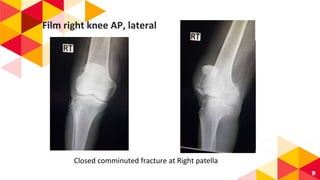

Film Right Knee: AP, lateral

Film right knee AP, lateral

Closed comminuted fracture at Right patella

“ Diagnosis : Closed comminuted fracture at right

patella